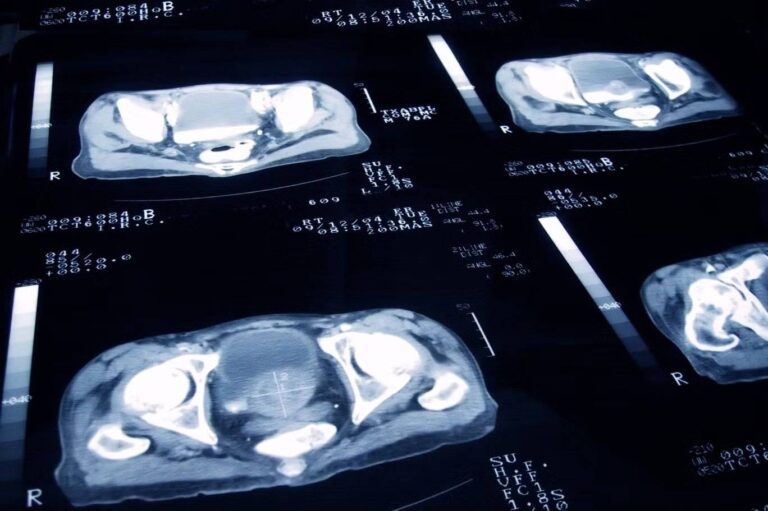

تصوير شعاعي لسرطان البروستاتا (غيتي) صحة ما سرطان البروستاتا الذي أصيب به بايدن وما خيارات العلاج المتاحة؟ by admin 23 مايو، 2025 written by admin 23 مايو، 2025 169 تأكدت إصابة الرئيس السابق الأسبوع الماضي بعد أن كشف فحص روتيني عن وجود كتلة سرطانية صغيرة اندبندنت عربية / غريغ إيفانز جو سمرلاد أريانا بايو . أعلن المتحدث باسم الرئيس الأميركي الأسبق جو بايدن الأحد الماضي أنه جرى تشخيص إصابته بنوع عدواني من سرطان البروستاتا، وقال إن بايدن (82 سنة) يبحث حالياً خيارات العلاج مع عائلته وأطبائه. وكان الأطباء قد اكتشفوا “عقدة صغيرة” في غدة البروستاتا خلال فحص روتيني أجري الأسبوع الماضي، وبعد إجراء مزيد من الفحوص تبين أنها إصابة بسرطان البروستاتا بدرجة “غليسون 9″، وقد انتشر إلى العظم. ويُعد سرطان البروستاتا أكثر أنواع السرطان شيوعاً بين الرجال في الولايات المتحدة، حيث يصيب نحو رجل من كل ثمانية خلال حياتهم، وعلى رغم أن هذا المرض يصيب غالباً الرجال فوق سن الـ 65 لكنه قد يُشخص في سن أصغر. وفي هذه المقالة نستعرض كل ما تحتاج معرفته عن سرطان البروستاتا، من الأعراض الباكرة وصولاً إلى سبل العلاج. ما هو سرطان البروستاتا؟ كما يشير الاسم فإن سرطان البروستاتا ينشأ في غدة البروستاتا، وهي غدة تقع عند قاعدة المثانة، وتُعد البروستاتا عضواً من الجهاز التناسلي الذكري، وتتمثل وظيفتها الأساس في إفراز سائل البروستاتا الذي يمتزج بالحيوانات المنوية لتكوين السائل المنوي. وتكون الغدة بحجم ثمرة الجوز تقريباً لكنها تميل إلى التضخم مع التقدم في العمر، وهي تحيط بالجزء الأول من الإحليل، وهو الأنبوب الذي ينقل البول والسائل المنوي. وعندما يتطور سرطان البروستاتا فإنه ينشأ عادة في الخلايا الخارجية للغدة، وتحديداً في ما يُعرف باسم “السرطان الغدي السنخي” Acinar Adenocarcinoma، وهو النوع الأكثر شيوعاً من سرطانات البروستاتا. ويحدث السرطان عندما تبدأ الخلايا غير الطبيعية في الانقسام والنمو بصورة خارجة عن السيطرة، وبحسب “جمعية السرطان الأميركية” فإن غالبية حالات سرطان البروستاتا تنمو ببطء ولا تنتشر عادة إلى أجزاء أخرى من الجسم، لكن عندما ينتشر السرطان إلى منطقة أخرى من الجسم يُعرف عندها باسم “السرطان النقيلي” Metastatic Cancer. ما هي أعراضه؟ تشمل أعراض سرطان البروستاتا، بحسب “جمعية السرطان الأميركية” التبول المتكرر أو صعوبة في التبول، والشعور بالحاجة إلى الشد أثناء التبول، والإحساس بعدم إفراغ المثانة بالكامل، ووجود دم في البول أو السائل المنوي. ومع ذلك فإن هذه الأعراض ليست دائماً دليلاً قاطعاً على الإصابة بسرطان البروستاتا، إذ قد يعاني كبار السن أعراضاً مشابهة نتيجة تضخم البروستاتا، وهي حال غير سرطانية. أما العلامات التي قد تشير إلى انتشار سرطان البروستاتا إلى أجزاء أخرى من الجسم وفقاً لـ “مايو كلينك” Mayo Clinic، فتشمل آلاماً في الظهر أو الوركين أو الحوض وضعف الانتصاب (الضعف الجنسي) ووجود دم في البول أو السائل المنوي مع فقدان غير مبرر في الوزن، ولمزيد من التفاصيل حول أعراض سرطان البروستاتا يمكن زيارة موقع “جمعية السرطان الأمريكية” أو “المعهد الوطني الأميركي للسرطان” US National Cancer Institute. أُعلن الأسبوع الماضي عن إصابة الرئيس السابق جو بايدن بسرطان البروستاتا (غيتي) ما هي أسباب الإصابة؟ على رغم أن السبب الدقيق للإصابة بسرطان البروستاتا لا يزال مجهولاً لكن هناك عوامل عدة تزيد احتمال الإصابة به، ووفقاً لـ “مراكز السيطرة على الأمراض والوقاية منها” الأميركية (CDC) فإن التقدم في العمر يُعتبر العامل الأكثر تأثيراً في زيادة خطر الإصابة، ويزداد احتمال الإصابة لدى بعض الفئات ومن بينها الرجال السود أو من لديهم تاريخ عائلي للإصابة بسرطان البروستاتا. ويُعد الرجال الأكبر سناً، بخاصة من تتراوح أعمارهم بين 65 و74 سنة، وكذلك الرجال السود غير المنحدرين من أصل إسباني، أكثر عرضة للإصابة بهذا النوع من السرطان. ما مدى شيوع سرطان البروستاتا؟ سرطان البروستاتا هو أكثر أنواع السرطان شيوعاً بين الرجال في الولايات المتحدة، ويقدّر “المعهد الوطني للسرطان” National Cancer Institute أن نحو 313780 شخصاً سيجرى تشخيصهم بسرطان البروستاتا عام 2025، وهو ما يمثل نحو 15 في المئة من جميع حالات السرطان الجديدة في البلاد، وفي عام 2022 كان هناك نحو 3518978 رجلاً يعيشون مع سرطان البروستاتا في الولايات المتحدة. ما مدى خطورة حال بايدن؟ كشف مكتب بايدن أن السرطان انتشر إلى العظام، مما يعني أنه تجاوز مرحلة السرطان الموضعي الباكر وأصبح في مرحلة أكثر تقدماً وخطورة، وبحسب الدكتور ماثيو سميث من مركز “ماساتشوستس جنرال بريغهام” لعلاج السرطان، فإن فرص النجاة تحسنت خلال العقود الأخيرة ويمكن للمصابين بسرطان البروستاتا النقيلي أن يعيشوا فترة تتراوح ما بين أربعة وخمسة أعوام، مضيفاً أن “المرض يمكن علاجه بصورة جيدة لكنه غير قابل للشفاء”. كيف يمكن علاجه؟ تتنوع طرق علاج سرطان البروستاتا بين المراقبة الدقيقة والعلاج الإشعاعي أو الجراحة، ووفقاً لمراكز السيطرة على الأمراض والوقاية منها، فإذا اعتقد الطبيب أن السرطان ينمو ببطء فقد يُنصح بالمراقبة النشطة، وهي متابعة مستمرة للحالة لرصد أي تطور أو ظهور أعراض جديدة، وبالنسبة إلى كبار السن، وبخاصة من لا يُتوقع لهم العيش لأكثر من 10 أعوام، فيفضل أحياناً اعتماد إستراتيجية “المتابعة اليقظة” التي تركز على علاج الأعراض فقط دون التدخل في علاج السرطان. ويجرى تحديد نوع العلاج بناء على مدى انتشار المرض، سواء كان محصوراً في غدة البروستاتا أو انتشر إلى أجزاء أخرى من الجسم، وفي بعض الحالات قد يخضع المرضى لجراحة تسمى “استئصال البروستاتا” لإزالة الغدة بالكامل، كما يُستخدم العلاج الهرموني لوقف الهرمونات التي تغذي نمو الخلايا السرطانية والعلاج الإشعاعي لتدمير هذه الخلايا، وعندما ينتشر السرطان إلى أجزاء أخرى من الجسم فقد يكون العلاج الكيماوي أو العلاج الموجه الخيار الأنسب، ومع ذلك ففي المراحل المتقدمة جداً من المرض قد يصبح الشفاء التام أمراً مستحيلاً. ما هو نظام غليسون وكيف كانت درجة بايدن؟ يعتمد الأطباء على مقياس غليسون لقياس مدى خطورة نمو خلايا السرطان، وتتراوح درجات غليسون ما بين 6 و10، إذ تشير الدرجات من 8 إلى 10 إلى سرطانات بروستاتا أكثر خطورة وتطوراً أسرع، وقد أوضح مكتب بايدن أن درجته كانت 9، مما يدل على أن السرطان الذي يعانيه من الأنواع الأكثر عدوانية وخطورة. © The Independent المزيد عن: جو بايدنسرطان البروستاتاالمعهد الوطني للسرطانانتشار السرطانالسرطان النقيليالعلاج الإشعاعيالتقدم في العمرمراكز السيطرة على الامراضجهاز التناسل الذكريمرض السرطانذوي البشرة السوداء 0 comment 0 FacebookTwitterPinterestEmail admin previous post متلازمة القلب المنكسر مرض أغلب إصاباته من النساء… ويقتل الرجال next post من تحديد النسل إلى تشجيع الإنجاب… تونس أمام تحديات شيخوخة السكان You may also like أعراض السرطان الصامتة: علامات خفية قد تكون قاتلة 28 أبريل، 2026 اختراق طبي: الذكاء الاصطناعي يكشف ألزهايمر بدقة غير... 11 مارس، 2026 طرق بسيطة لتخفيف أعراض التهاب المفاصل 11 مارس، 2026 سرطان الرئة الأكثر فتكا… والكشف المبكر ينقذ الآلاف 7 مارس، 2026 فتيات يقعن في فخ PPD مع موسم الحناء... 7 مارس، 2026 مفاجأة علاجية… عقار قديم يُظهِر فائدة جديدة للذاكرة 5 مارس، 2026 مسنون يقاومون الخرف: ما سر ذاكرتهم الخارقة؟ 4 مارس، 2026 تغييرات طفيفة في نمط الحياة تقلل من خطر... 26 فبراير، 2026 مارسه صباحاً ومساءً… نشاط يومي قد يبطئ السرطان 24 فبراير، 2026 (7 تغيرات) في الشخصية في منتصف العمر قد... 24 فبراير، 2026